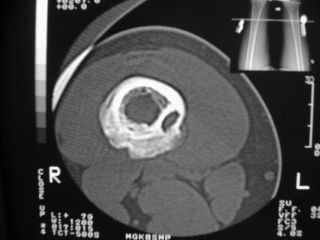

Здравствуйте, уважаемые коллеги!Представляю вашему вниманию интересный случай и пока что непонятный для меня в диагностическом плане. На днях в наше отделение (детской ортопедии и травматологии) поступил 13-летний мальчик по направлению из поликлиники с диагнозом: остеома нижней трети правого бедра.

Анамнез практически никакой: в следствие травмы (растяжение связок коленного сустава) от 07.11.2004 выполнены Rg-граммы в травмпункте и обнаружено опухолевидное образование. Первичные Rg-граммы я не публикую, так как они заметно худшего качества, да и динамики за прошедшие три недели не отражают. Болевой синдром купирован в течение трёх дней. В настоящий момент мальчика ничего не беспокоит. Ходьба не нарушена, опухоль пальпируется с трудом по задней поверхности в н\3 правого бедра, пальпация безболезненна, объем движений в суставах правой нижней конечности полный и симметричный. Кожа над опухолью не изменена.В нашей клинике проведено дополнительное обследование: общие анализы крови и мочи, биохимия крови без особенностей. Выполнены Rg-граммы на цифровом Siemens обычные и продольные томограммы срезами 3-5 мм, а также компьютерная томография поперечными срезами по 5 мм. Прошу обратить внимание, что на приведённых томограммах видны две полости 10х15 мм и 15х60 мм. Также имеются два опухолевидных образований наслаивающихся друг на друга: уплощённое и вытянутое 10х100 мм и элипсовидной формы 15х30 мм. Это хорошо заметно на фото a_1.jpg c_1.jpg и d_1.jpg. Плотность внутри полостей 125% от плотности костномозгового канала, плотность наружного опухолевидного образования 55% от плотности кортикального слоя. Также отмечается линия перелома по центру наружного опухолевидного образования.Исходя из полученных данных мнения в плане диагноза несколько разделились от 1)сочетания кортикальной фиброзной дисплазии и латентно протекавшего маршевого перелома н\3 правого бедра до 2)остеосаркомы. В отношении первого варианта не сходится отсутствие клиники при переломе такой крупной кости как бедро, второй вариант вообще оставлю без комментария, ибо некомпетентен. Хотелось бы услышать мнения коллег, с удовольствием ознакомлюсь с любыми предположениями и замечаниями.С уважением, Александр Е. КлоковОтделение детской ортопедии и травматологииБСМП г. Мурманска.